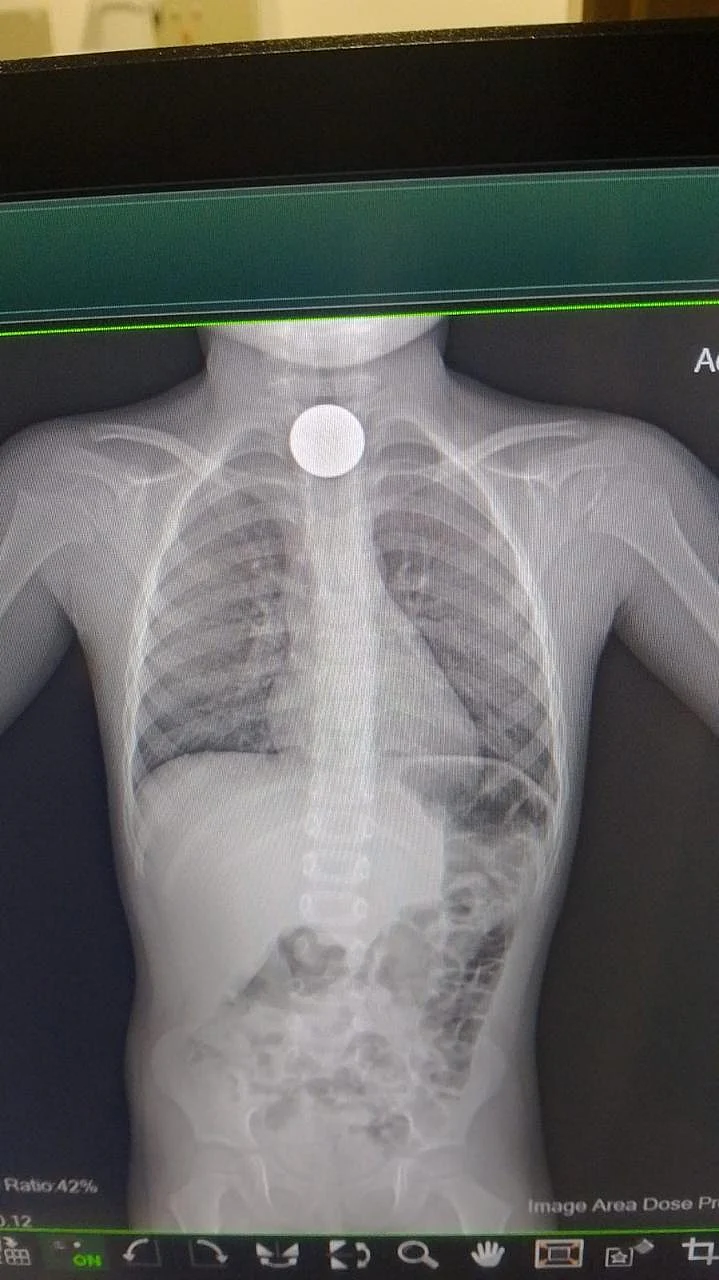

Muhammad Shahzain Awan was brought to Medcare Royal Speciality Hospital in Al Qusais in distress, with doctors quickly identifying that the coin had become lodged in his upper oesophagus, an area where even slight movement can lead to serious complications.

The medical team moved swiftly, carrying out an emergency endoscopic procedure to remove the object. The coin was retrieved in just two minutes using a minimally invasive technique, and the child was stabilised soon after.

“The procedure was complex and delicate, especially since the patient was a four-year-old child. Children typically have narrower passages, making it challenging to use endoscopy equipment and accessories,” said Dr Priyadarshini.